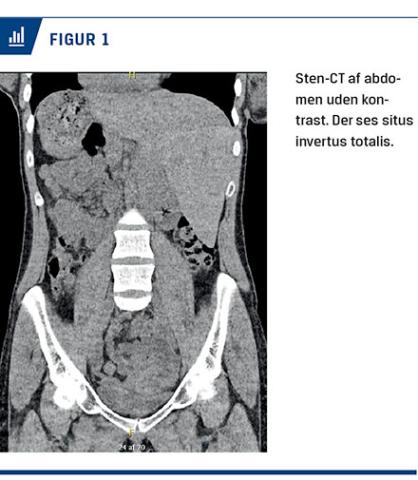

I vores kollegas journal var der et røntgenbillede af columna, taget pga. mistanke om fraktur efter et trafikuheld tre år forinden. Her var knoglerne, men ikke bløddelene beskrevet. Hjerteskyggen sås også her med apex mod højre, desuden sås en halskæde med et hjerte, der pegede i samme retning (Figur 2).